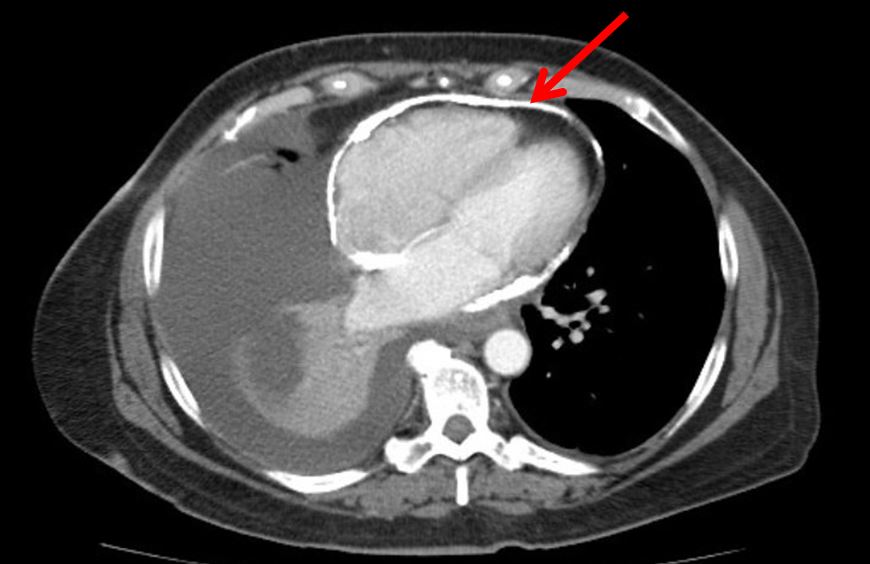

A 58-year old woman was admitted to the hospital for further evaluation of a recurrent right-sided, exudative pleural effusion requiring three prior therapeutic thoracenteses in the past month. She had no history of malignancy, radiation exposure, or recent infectious symptoms. Echocardiogram demonstrated a calcified pericardium with septal bowing into the left ventricle during inspiration. CT chest demonstrated a moderate right-sided pleural effusion with circumferential pericardial calcification. Cardiac MRI showed similar circumferential pericardial thickening with respirophasic variation of the interventricular septum consistent with constrictive physiology. Simultaneous right and left heart catheterization showed elevated and equal right and left ventricular diastolic pressure tracings as well as respirophasic discordance between the right and left ventricular systolic pressures.